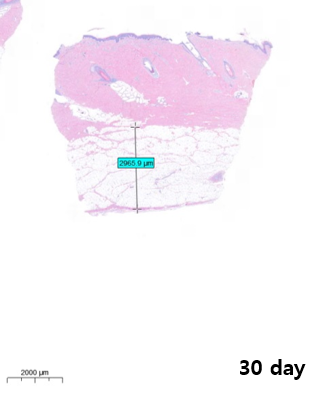

실제 노블쉐이프 시술 후 피하지방층의 두께 변화를 관측한 단면도입니다.

보면 시술 직후부터 한 달까지 지방층의 두께가 점차 감소하는 모습을 확인할 수 있는데요. 실제 두께 변화를 보면 시술 직후와 한 달 후 약 40% 이상 지방층 두께가 감소한 결과를 보였습니다.

바디 리프팅 시술을 받아보셨던 환자분들이라면 아시겠지만 바디 리프팅 시술은 시술 직후에는 큰 변화를 보이지 않습니다. 시간이 지나면서 지방 세포가 분해되고 축소하면서 서서히 효과가 나타나게 되는데요.

개인차는 있지만 보통 시술 후 2~3주 정도가 지나면 어느 정도 효과를 체감할 수 있습니다.